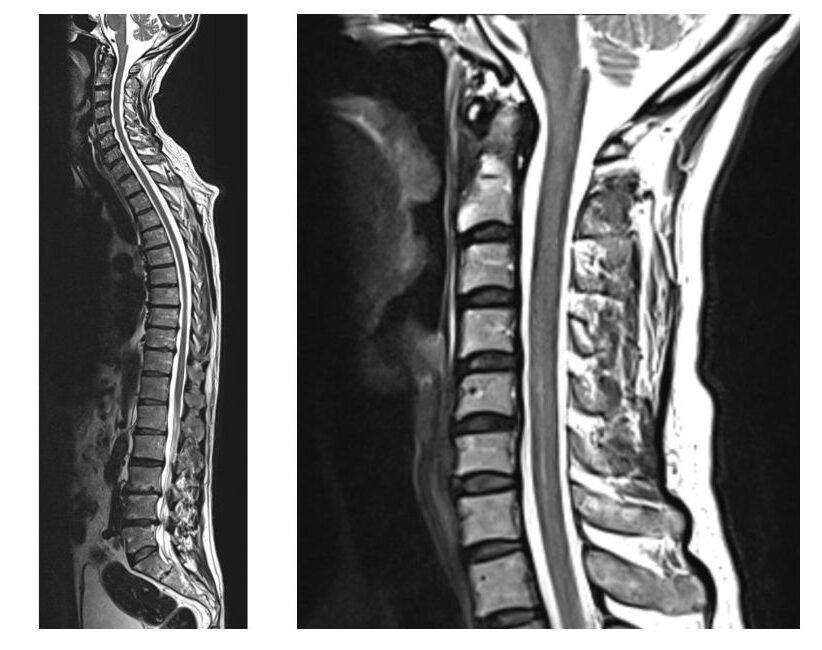

Auf unserer Seite finden Sie umfangreiche Informationen zu orthopädischen Beschwerden und Erkrankungen. Von der Arthrose über Bandscheibenvorfälle bis hin zu Kreuzbandriss und weiteren Sportverletzungen: wir geben Ihnen einen Überblick über die häufigsten orthopädischen Krankheitsbilder, wie sie behandelt werden können und inwieweit ein Bildgebungsverfahren, wie eine (z.B. MRT Knie, Rücken MRT) bei der Diagnose bei der Diagnose unterstützend wirken können.

Viele Betroffene suchen online nach den Ursachen oder Behandlungsmöglichkeiten von Rückenschmerzen, Bänderriss am Fuß oder Bandscheibenvorfall. Einige der orthopädische Beschwerden oder Verletzungen benötigen zu Behandlung eine Bildgebung und Therapie. Alle relevanten Informationen lesen Sie in den jeweiligen Beiträgen.